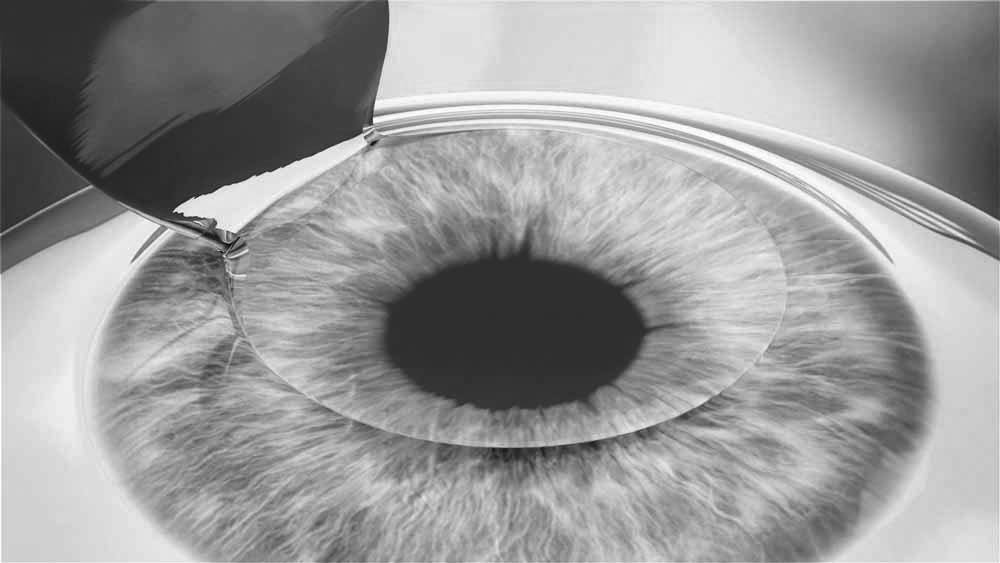

ল্যাসিক (LASIK- Laser Assisted in Situ Keratomileusis) চশমা বিকল্পে প্রযুক্তগিত উৎকর্ষের এক অত্যাধুনিক আবিষ্কার।এটি এক অত্যাধুনিক চক্ষু লেজার প্রযুক্তি যা এক্সাইমার লেজারের সাহায্যে করা হয়। ল্যাসিক চিকিৎসায় ব্যবহৃত এক্সাইমার লেজার আমাদের চোখের একেবারে সামনে কর্নিয়ার মাঝখানের এক চতুর্থাংশ থেকে এক তৃতীয়াংশ অত্যন্ত নিখুঁতভাবে পাতলা করে দেয়। এটি এমনই এক প্রযুক্তি যাতে চোখের বাইরে বা চোখের মধ্যেও কোনো লেন্স বসান হয় না।ল্যাসিক করাতে হাসপাতালে থাকতে হয় না, অজ্ঞান করা হয় না, এমন কি কোন ইনজেকশন বা ব্যান্ডেজও দিতে হয় না। শুধু ড্রপ দিয়ে চোখ অবশ করে ল্যাসিক করা হয়। দুই চোখে ল্যাসিক করতে সময় লাগে মাত্র ৫ থেকে ৭ মিনিট যদিও আসল লেজার সময় মাত্র কয়েক সেকেন্ড প্রতি চোখে। আধ ঘন্টা পরই রোগী বাসায় যেতে পারে। অপারেশনের পরদিন চোখ দেখে কেউ বলতেও পারবে না যে অপারেশন হয়েছে।

- ল্যাসিক অপারেশনের প্রথম পদক্ষেপ মাইক্রোকেরাটমের সাহায্যে চোখের কর্নিয়ায় একটি ফ্ল্যাপ তৈরি করা হবে। এ সময় চোখের উপর একটু চাপ লাগবে এবং আপনি কয়েক সেকেন্ড সবকিছু ঝাপসা দেখবেন কিন্তু কোনো ব্যথা পাবেন না। আপনার কাজ হবে কোনোদিকে চোখ না ঘুড়িয়ে স্থীরভাবে তাকিয়ে থাকা।

- এই পর্যায়ে চোখের কর্নিয়ায় তৈরিকৃত ফ্ল্যাপটি ইন্সট্রুমেন্টের সাহায্যে তুলে একপাশে সড়িয়ে রাখা হবে।

- লেজার প্রয়োগ শেষ হলে চোখ ধুয়ে পরিষ্কার করে কর্নিয়ার সেই সড়িয়ে রাখা ফ্ল্যাপটি আবার নামিয়ে দেয়া হবে এবং অপারেশন শেষ করা হবে।